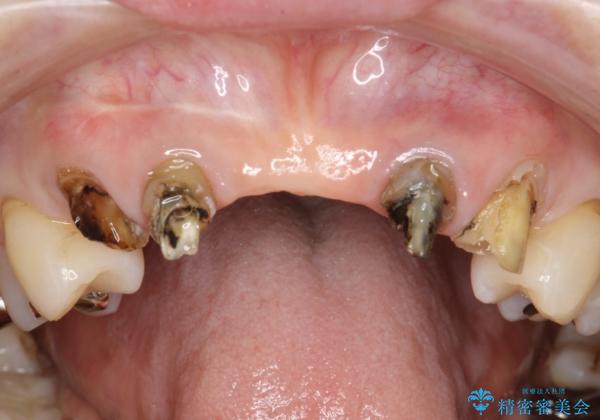

- 仮歯の製作、古い土台(メタルコア)の除去まで行い、根管治療は専門医に依頼

→根管治療終了後、ファイバーコアを築造し、新しいセラミックブリッジを製作した。

一見きれいにはいっているセラミックも、はずして中の状態をみるとひどいことが多い。これは、中の土台の状態や処理のクオリティは、短期的には問題を起こしづらく、患者さんには見えない部分だからです。